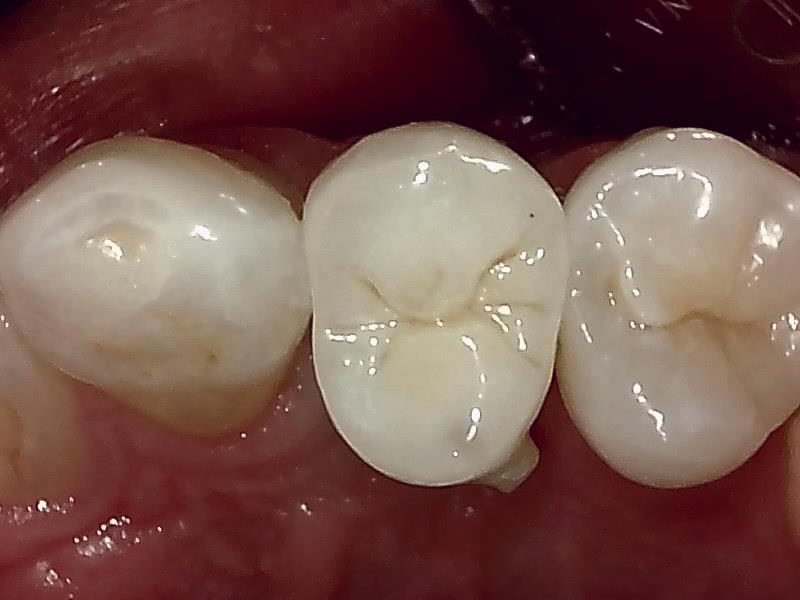

インプラントの上部構造 (左上)

(ジルコニアセラミッククラウン)

術後、とても経過良好です。

咬合正面観

口蓋側面観

頬側面観